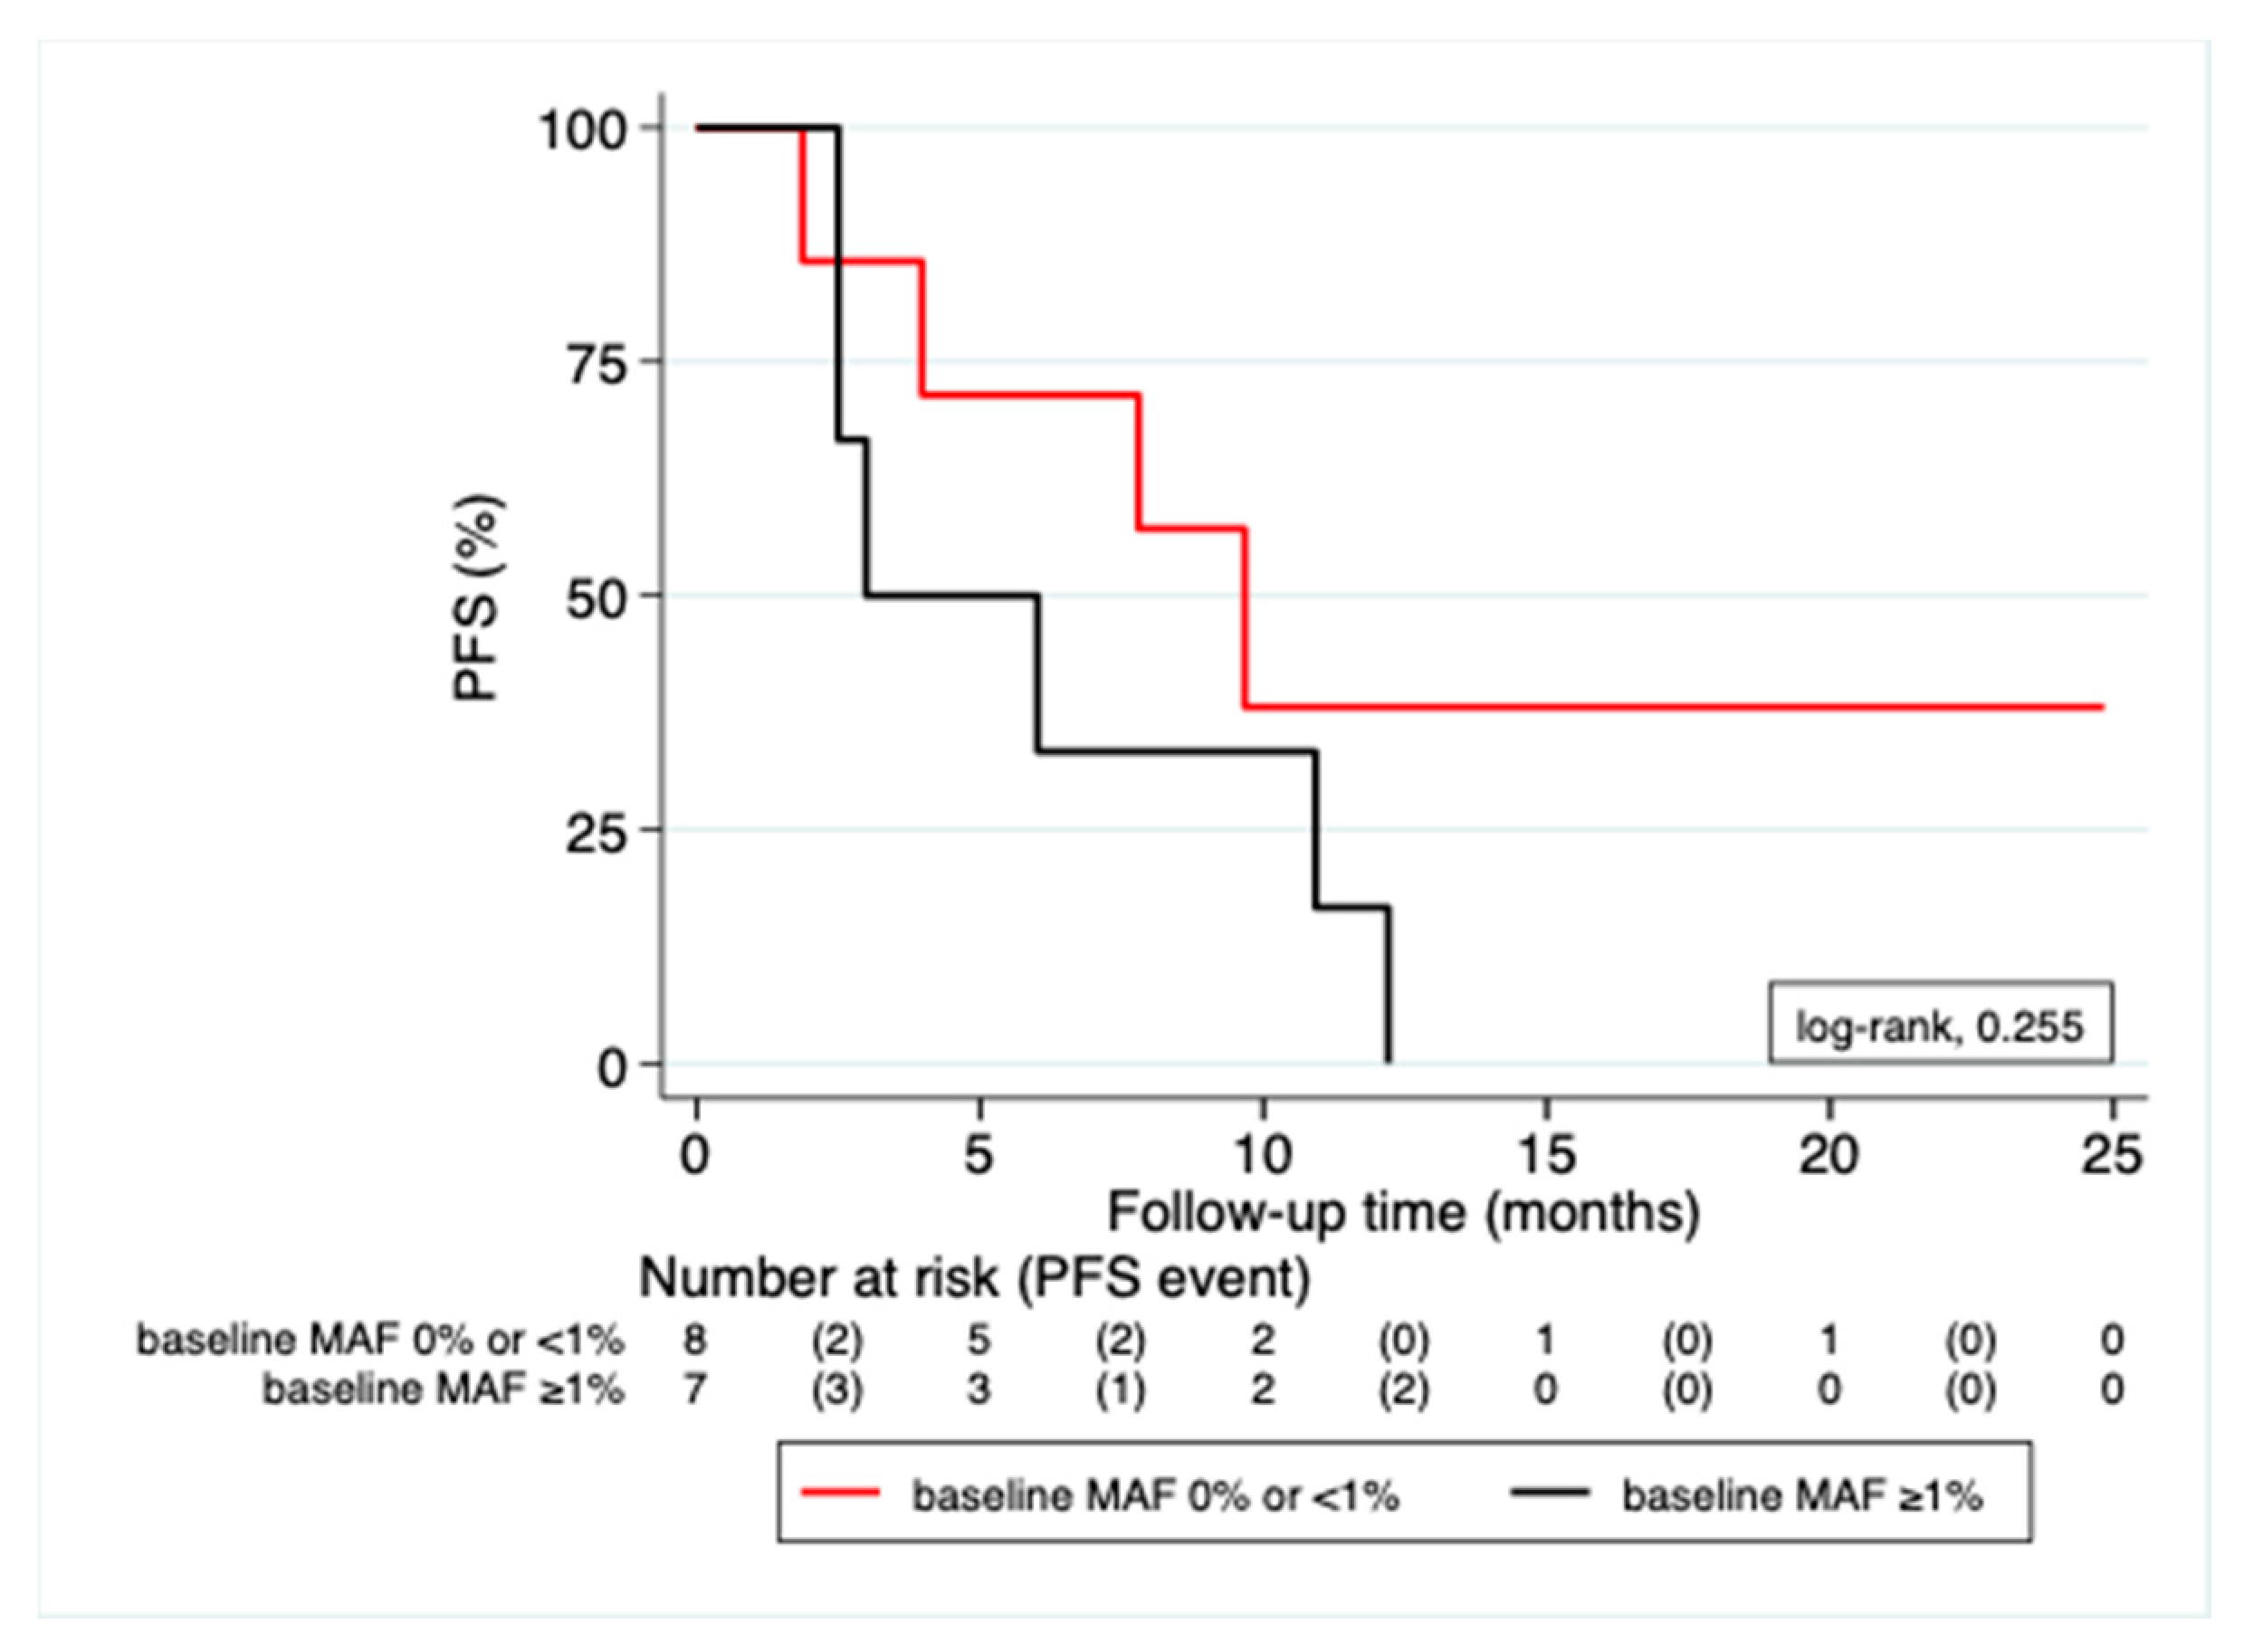

3.3. Correlation of MAF Levels with Radiological Response